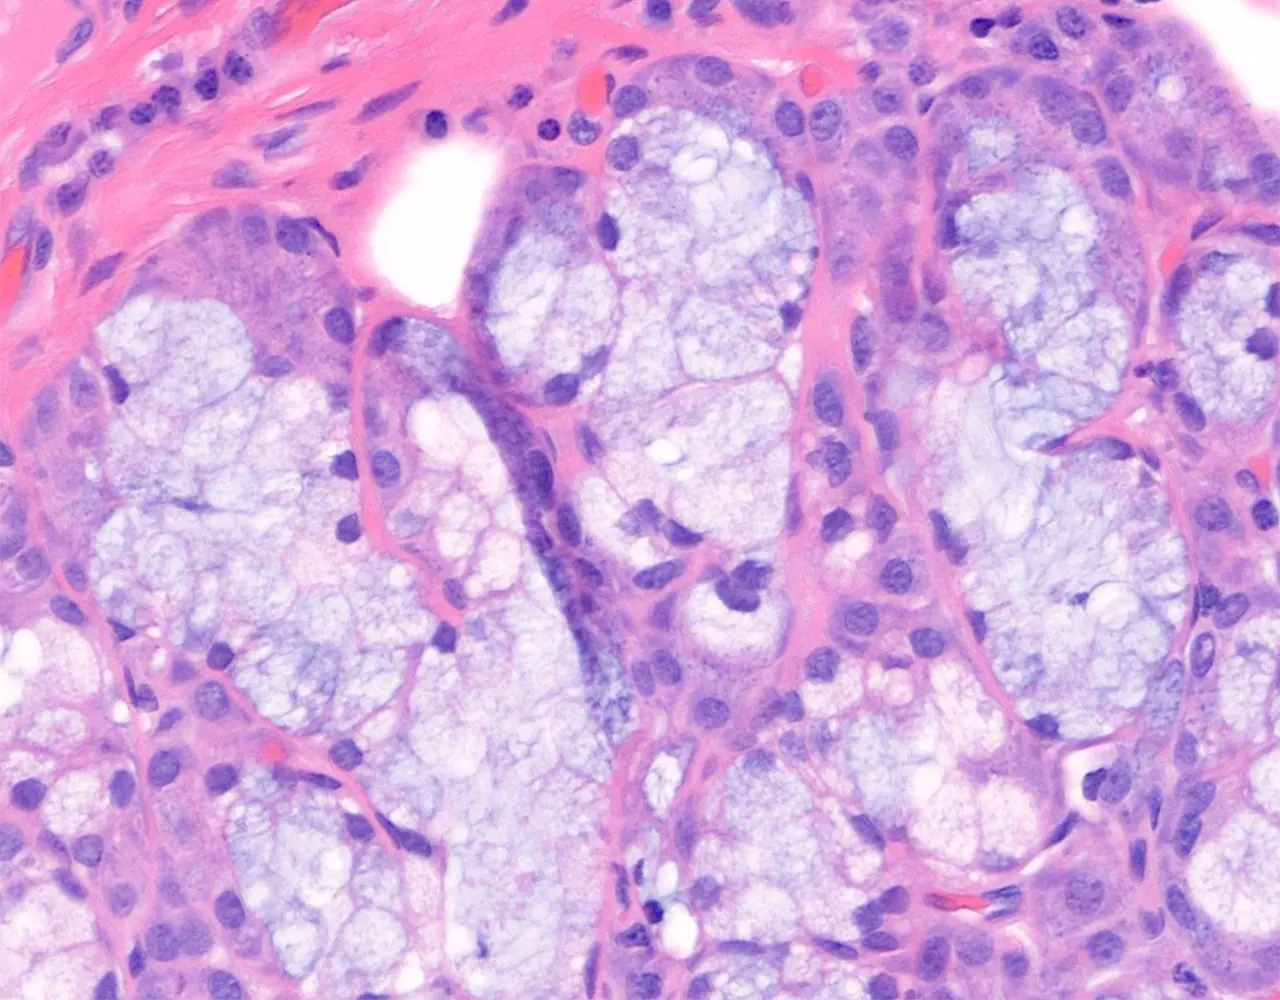

- Microscopically, the functional structure of a salivary gland consists of secretory acini and a duct system.